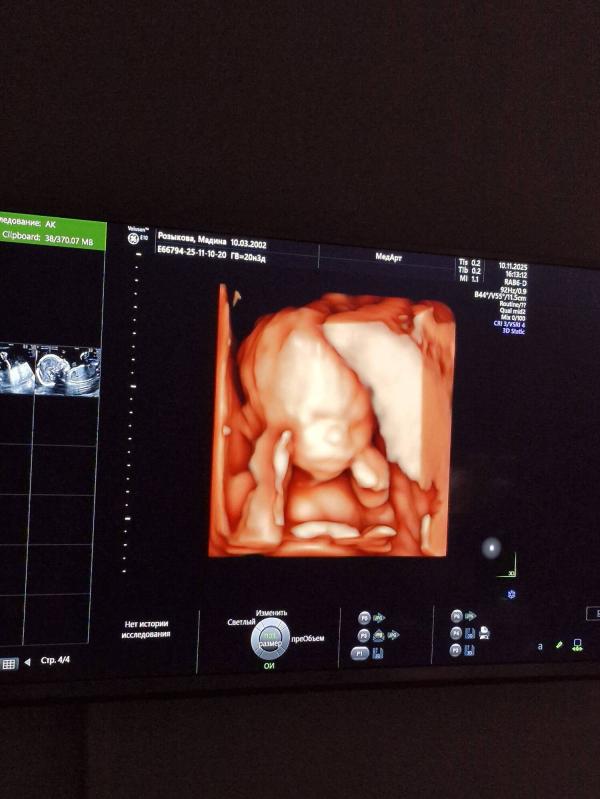

Мой сыночек, который не хотел себя ни в какую показывать. Так и прятал лицо. За то попой вверх лежал, и сразу показал все свои прелести..там даже врачом не надо быть, чтоб понять, кого ждешь🤣🤍

Ма Ша Аллах, такой активный, ручками ножками дергал, не давал врачу себя осматривать. В итоге лицо так и не показал..

Сделала все, и Альхамдулиллах повернулся хоть, носик смогла врач посмотреть. Но лицо до последнего не показывал.

Мамин серьезный 🤍

А сегодня прям попкой лежал вверх, и там реально все очертания были уже😅🤣